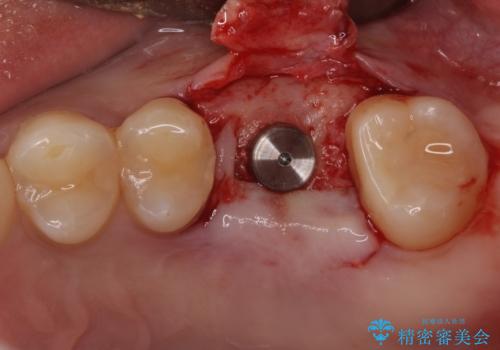

矯正治療とインプラント治療を同じ歯科医師が担当することで、通常見られるような複数医院を行き来する煩雑さや、複数担当医の見解の違いによる治療の遅滞といった煩わしさは一切なく、スムーズに治療を進めることができました。

安定して咬めるようになり、患者様には大変満足していただきました。